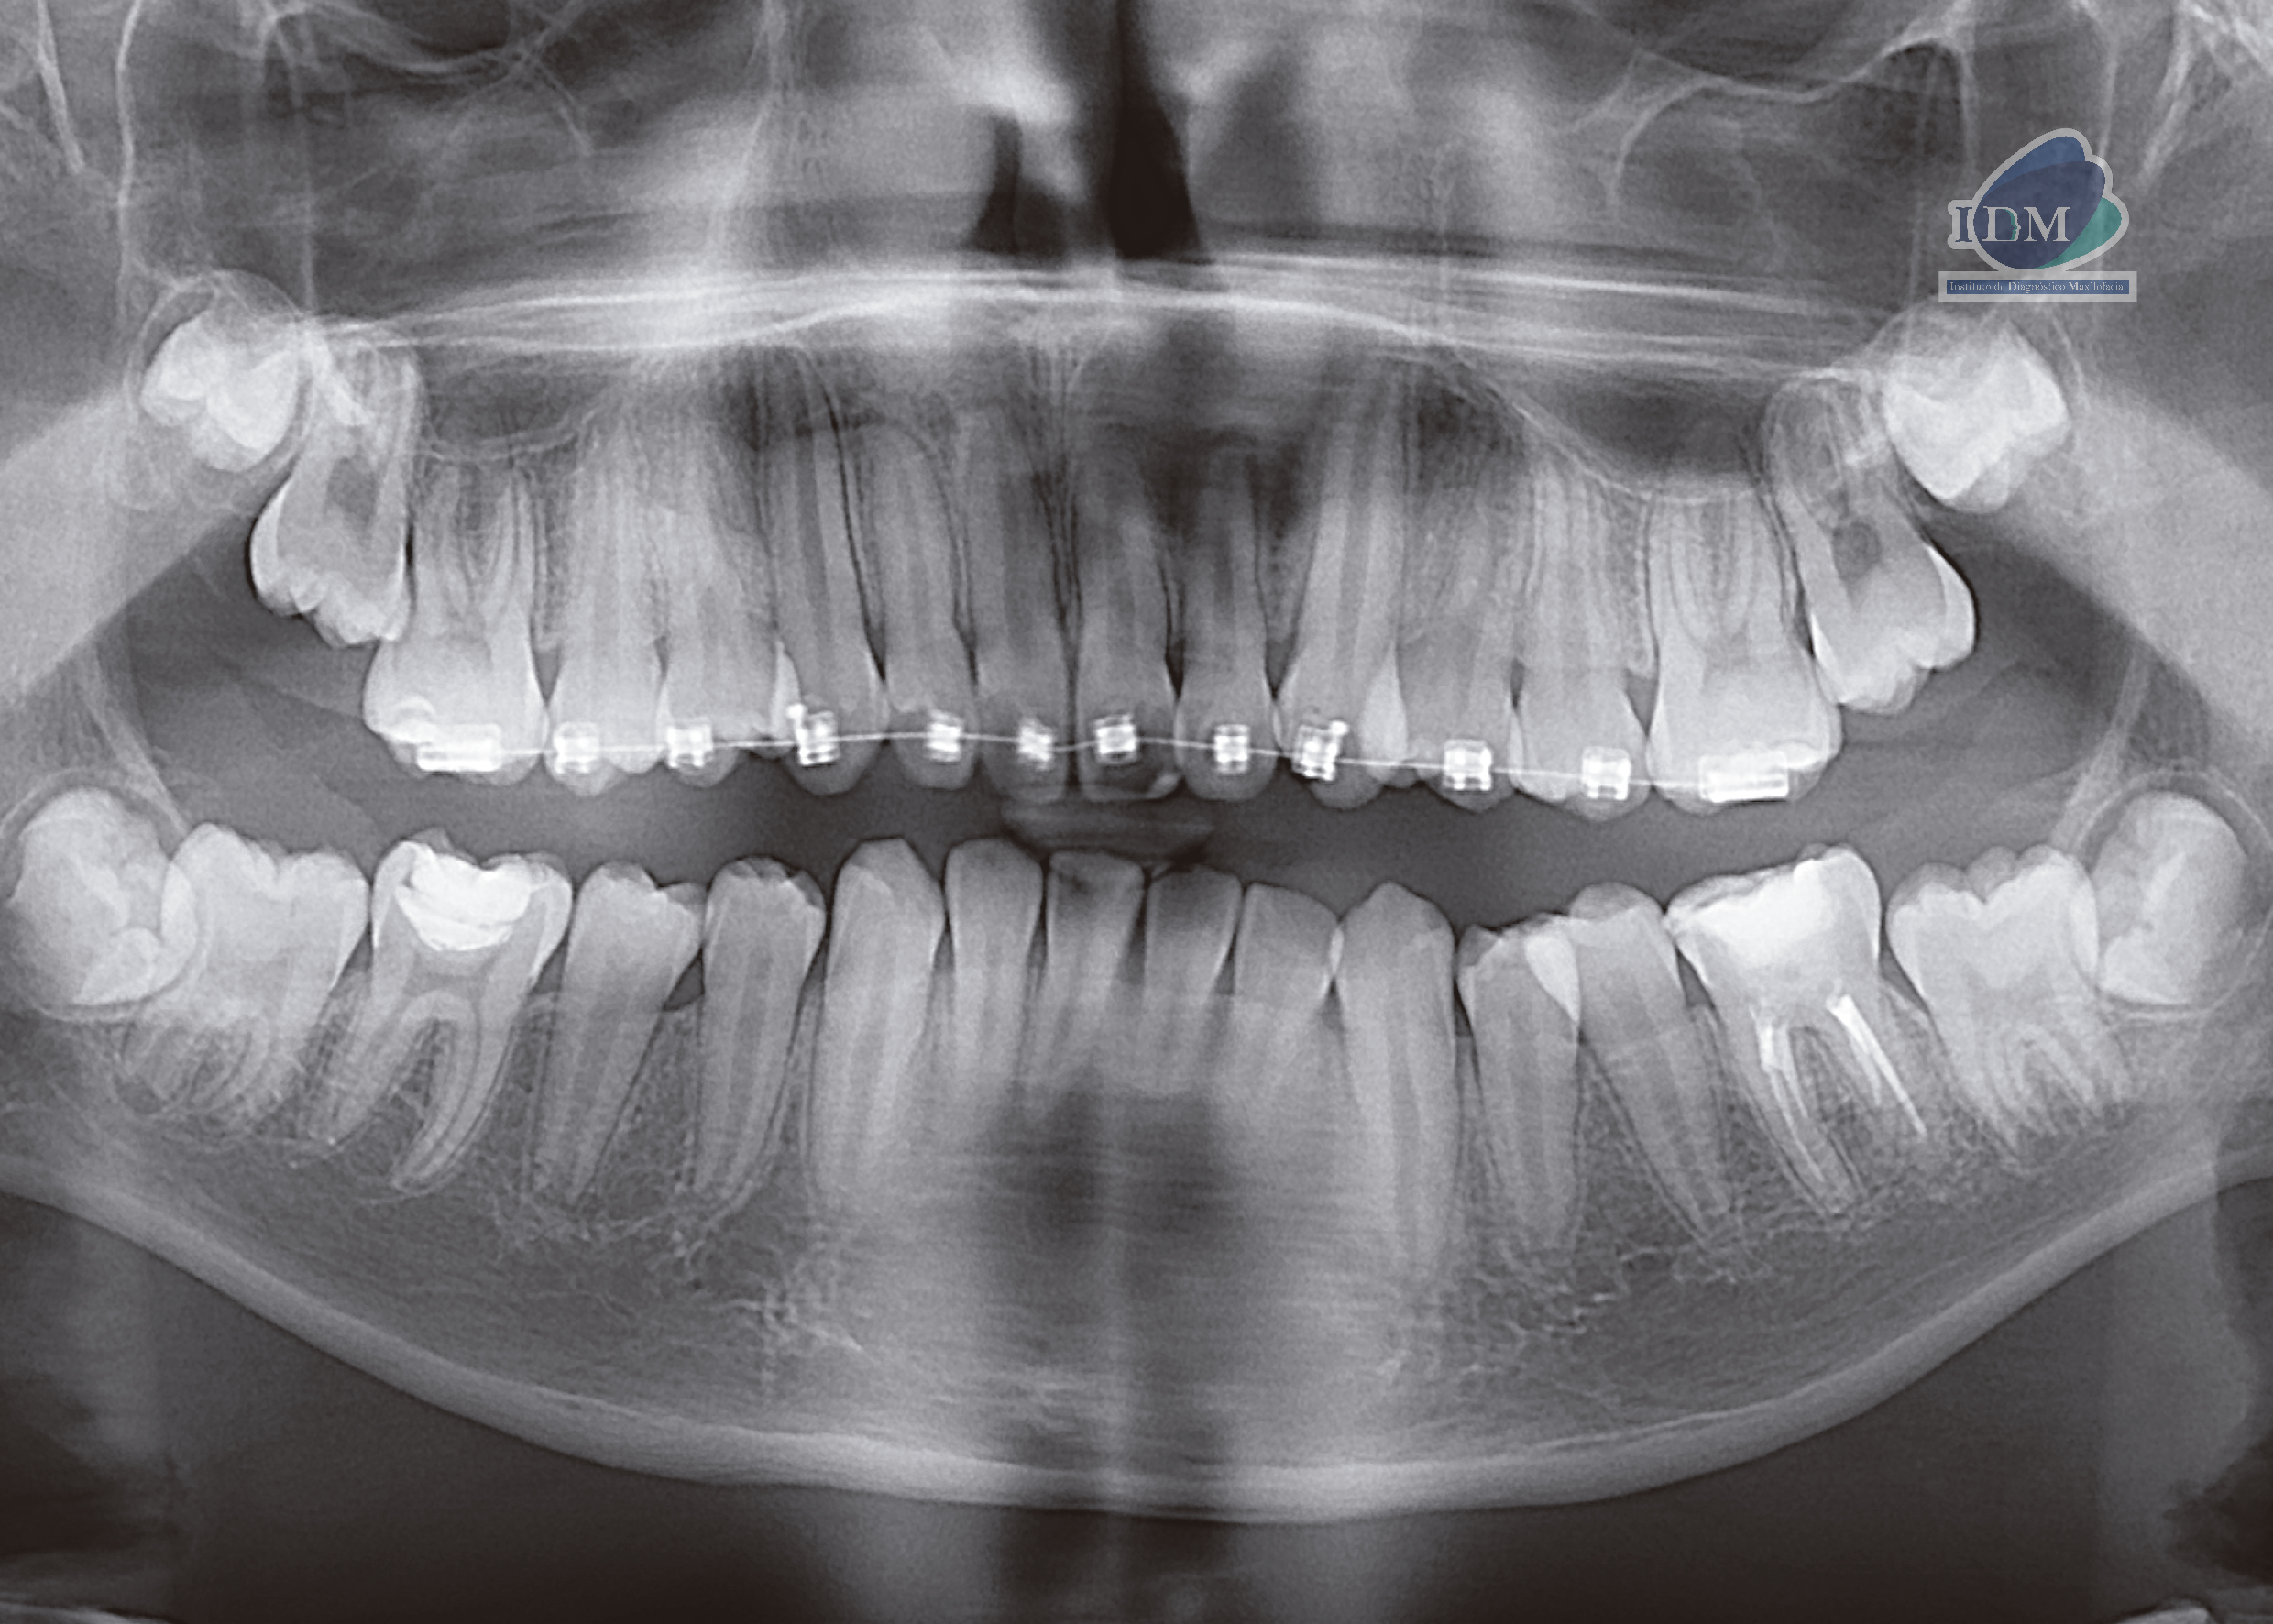

Radiografia Panorámica

En la radiografía panorámica (Figura 1), se aprecia mineralización segmentada de los procesos estilohioideos, apartotologia fija de ortodoncia en maxilar superior, pieza 36 presenta restauracion oclusal y obturación de conductos, pieza 46 restauracion oclusal.